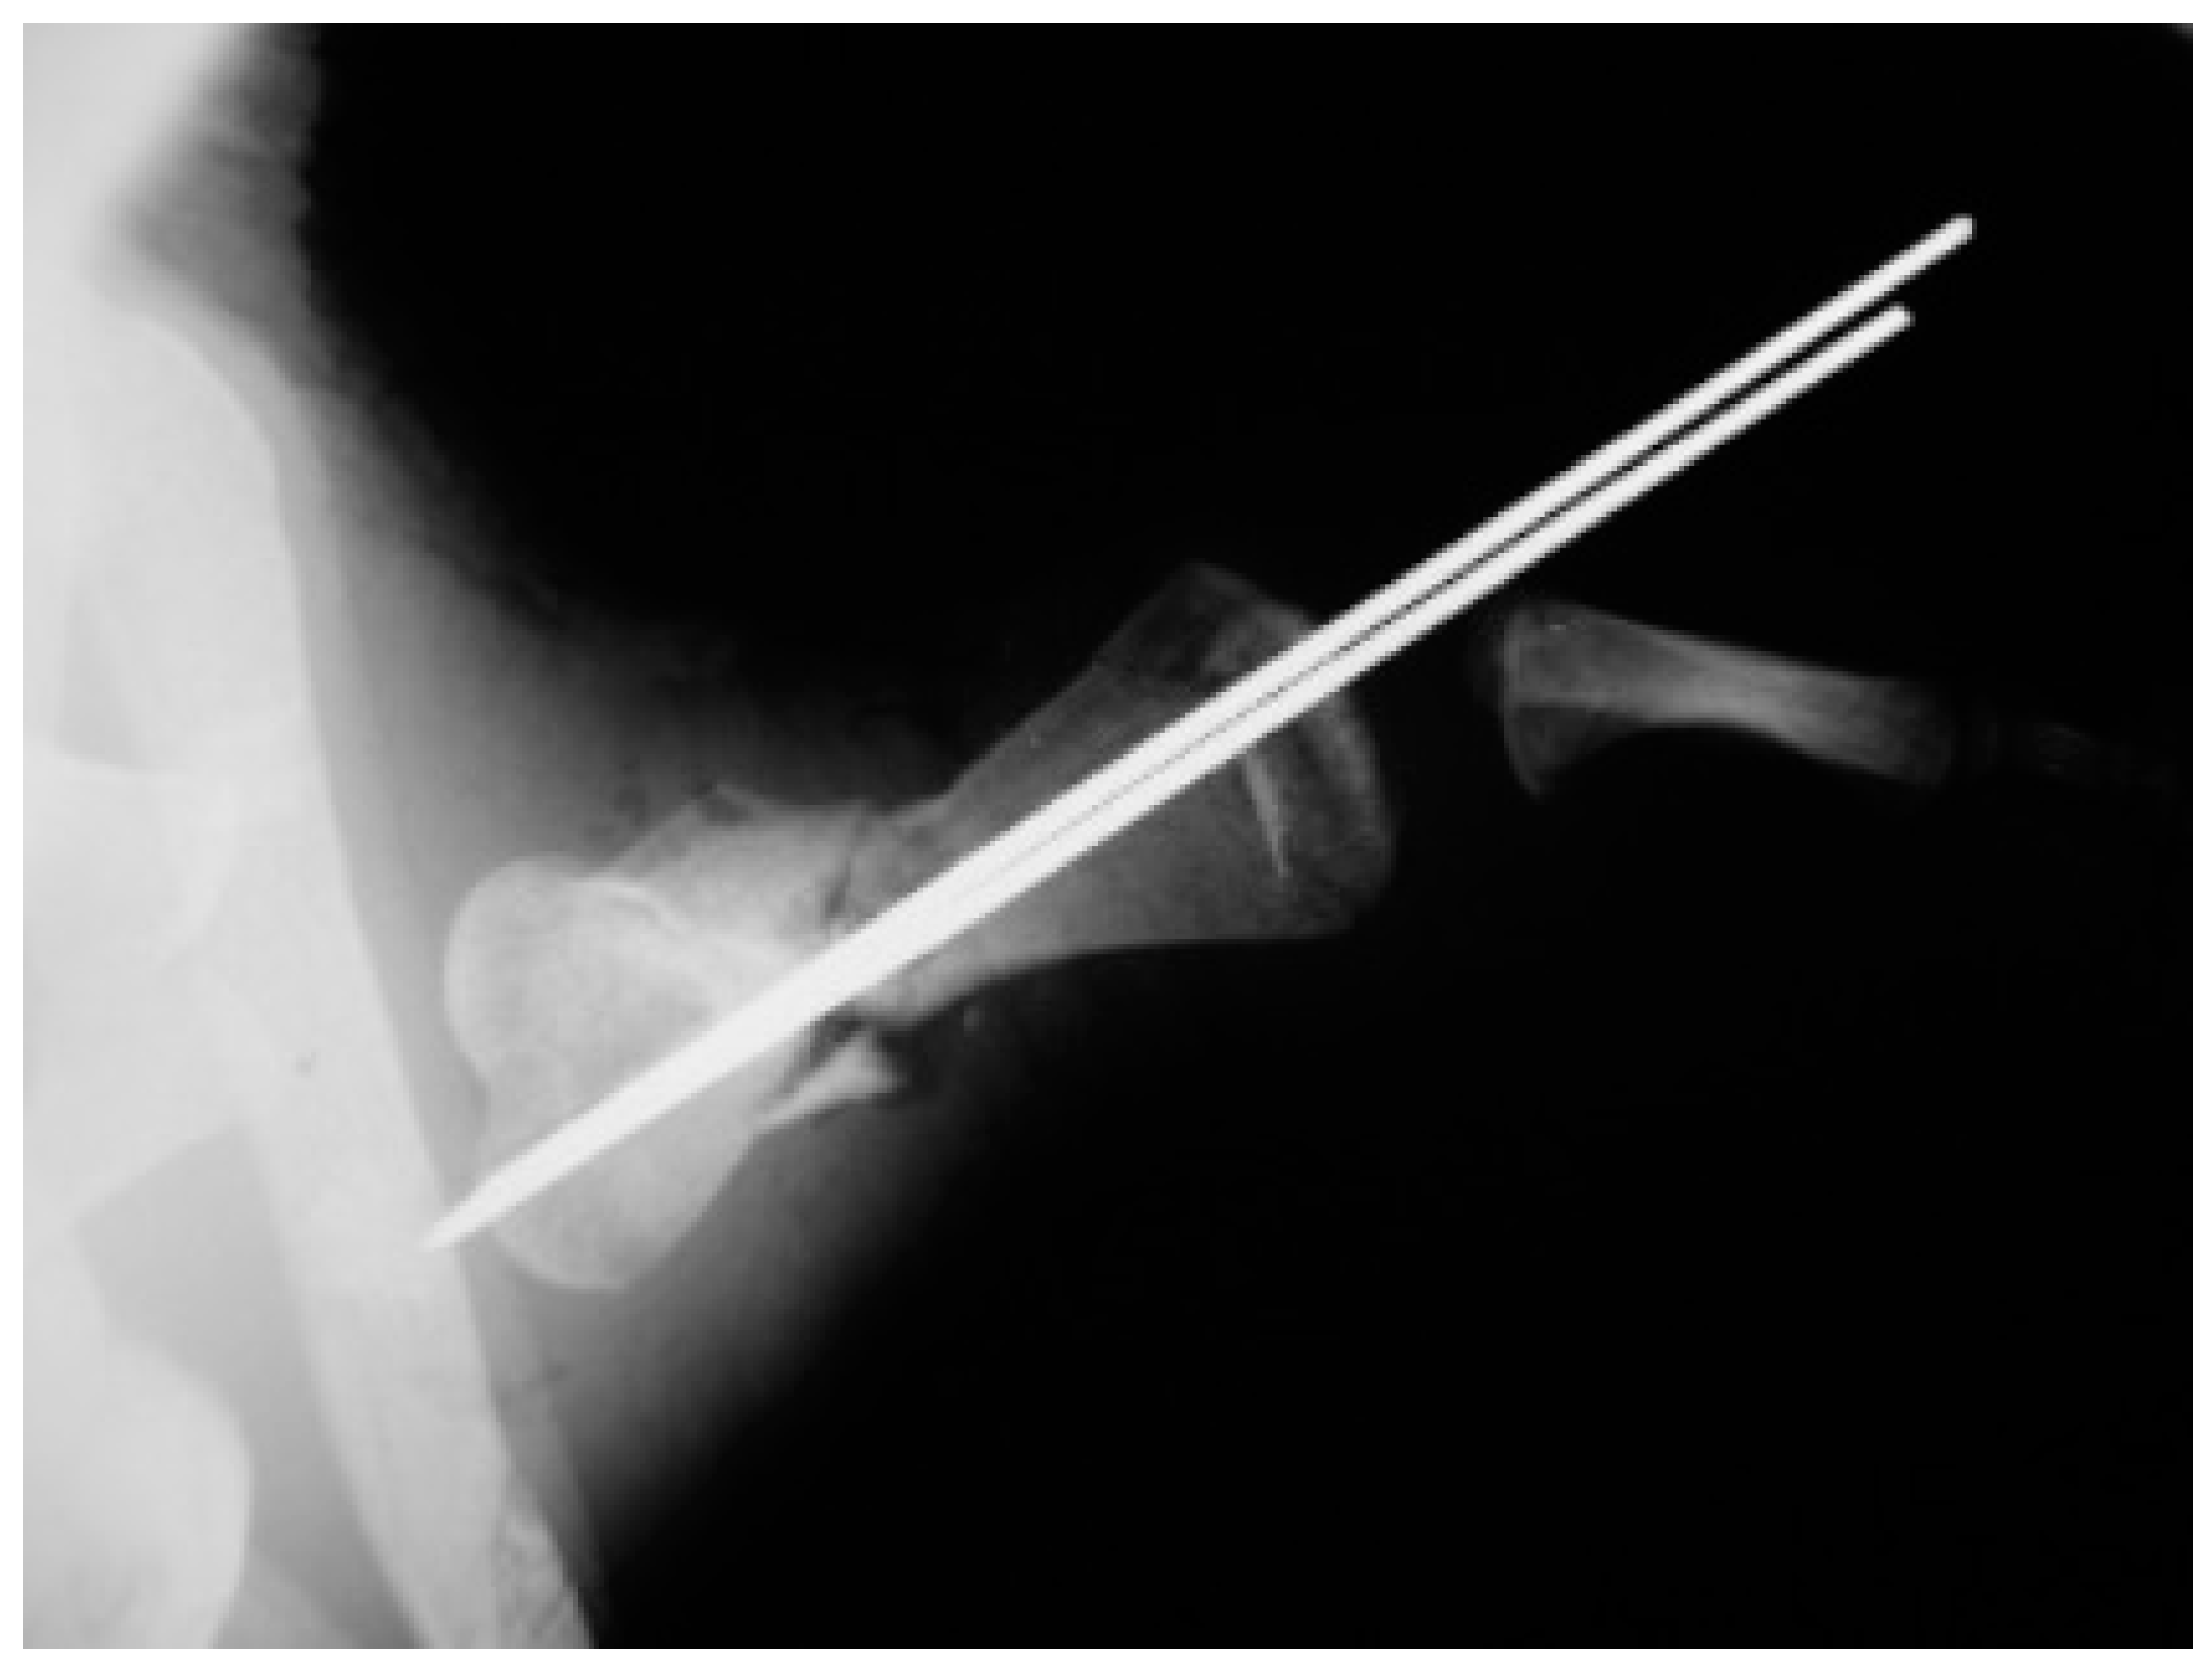

A juvenile sea turtle was presented to the Sea Turtle Clinic (STC) of Veterinary Medicine Department of the University of Bari with an entanglement lesion affecting the right front flipper. On admission, the sea turtle was measured and underwent a complete physical examination; curved carapace length (CCL) from notch to tip ranged 41 cm, curved carapace width (CCW) was 37 cm, and the weight was 18 Kg. The turtle appeared responsive but weak and dehydrated. Clinical evaluation of the musculoskeletal system performed out of the water showed swelling of the right front flipper and evidence of pain on deep palpation of the respective brachial muscle. A reduction in the right front flipper’s range of motion was observed when the turtle was examined in the water. Radiographic assessment, in dorso-ventral (D-V) and Caudo-Cranial (C-C) projections, indicated detachment of the distal epiphysis of the humerus, compatible with a type II Salter-Harris fracture, together with a transverse diaphyseal fracture (Figure 1). The turtle underwent general anesthesia, and the craniodorsal access to the humeral diaphysis was performed. The epiphyseal fracture was reduced by closed surgery and fixed using two crossed 2.5 mm Kirschner pins, introduced backward from the distal stump and brought out through the hyperflexed humerus-radio-ulnar joint. The same pins used to fix the epiphyseal fracture were inserted into the proximal stump to fix the diaphyseal fracture. After checking the stability of the fractures reductions, the surgically sectioned soft tissues were reconstructed, and post-operative radiographs were performed. Follow-up was performed after the surgery at 2, 4, 12, 16, and 24 months, when the turtle was released at sea. Three months after its release at sea, the turtle was caught dead in a fishing net at a depth of 40 m. To determine the evolution of bone repair from turtle release to death, the right humerus was removed for histological and histomorphometry analyses. Immediately after explant, the humerus was fixed in 4% buffered paraformaldehyde, dehydrated in ethanol, and embedded in methylmetacrylate. Serial cross sections, 750 µm thick, were cut at both the diaphyseal and epiphyseal fracture gaps using a circular diamond-bladed saw (Gillings Hamco) and were ground to a thickness of 100 µm. Sections were placed on a specimen holder and microradiographed using a microradiograph (Constant 1-K, Ital Structures, Italy) at a prefixed distance from the X- ray generator of 9.5 cm. X-ray exposure was set up at 8 kV and 14 mA. Contact microradiographs were obtained on Kodak high-resolution film (SO 343, Eastman Kodak Co., Rochester, NY, USA), developed with Kodak HC-110, fixed in Kodak UNIFIX, washed in distilled water and then airdried at room temperature. Sections were subsequently stained with 1% toluidine blue (pH 3.7) for mineralized tissue. Four separate levels were selected, three belonging to the mid-diaphyseal fracture gap, and one level to the epiphyseal fracture gap: the first and the fourth levels corresponded to the proximal and distal part of the callus, respectively, and the second and third levels to the center of the fracture (Figure 2). As a control, the left humerus, which had never been fractured, was processed with the same procedure. On the stained sections, using a Nikon DS-5 camera connected to a stereomicroscope (SMZ800, Nikon Europe B.V., Amstelveen, The Netherlands) and a DS camera control unit, the callus extension was measured and the amount of new laid down bone, cartilage, and fibrous tissue, expressed as percentage ratio of the entire section, were evaluated. Histomorphometry was performed using Nis-Elements BR analysis software (Nikon Europe B.V.).

Figure 1. Caudocranial radiograph of the anterior right flipper showing transverse diaphyseal and the type II Salter-Harris fractures.